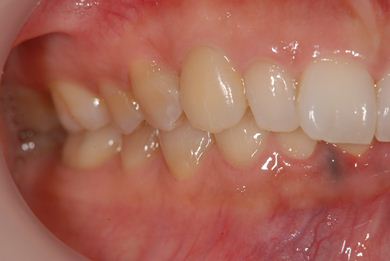

性別/年齢 女性 / 37歳

主訴 歯の差し歯が少しぐらつく。歯ぐきが違和感を感じる。

治療方針 抜歯と同時にインプラントを埋入し、治療期間を短縮する。

治療内容 インプラント1本(抜歯即日スピードインプラント)、メタルボンドセラミック1本

治療前

• 治療前